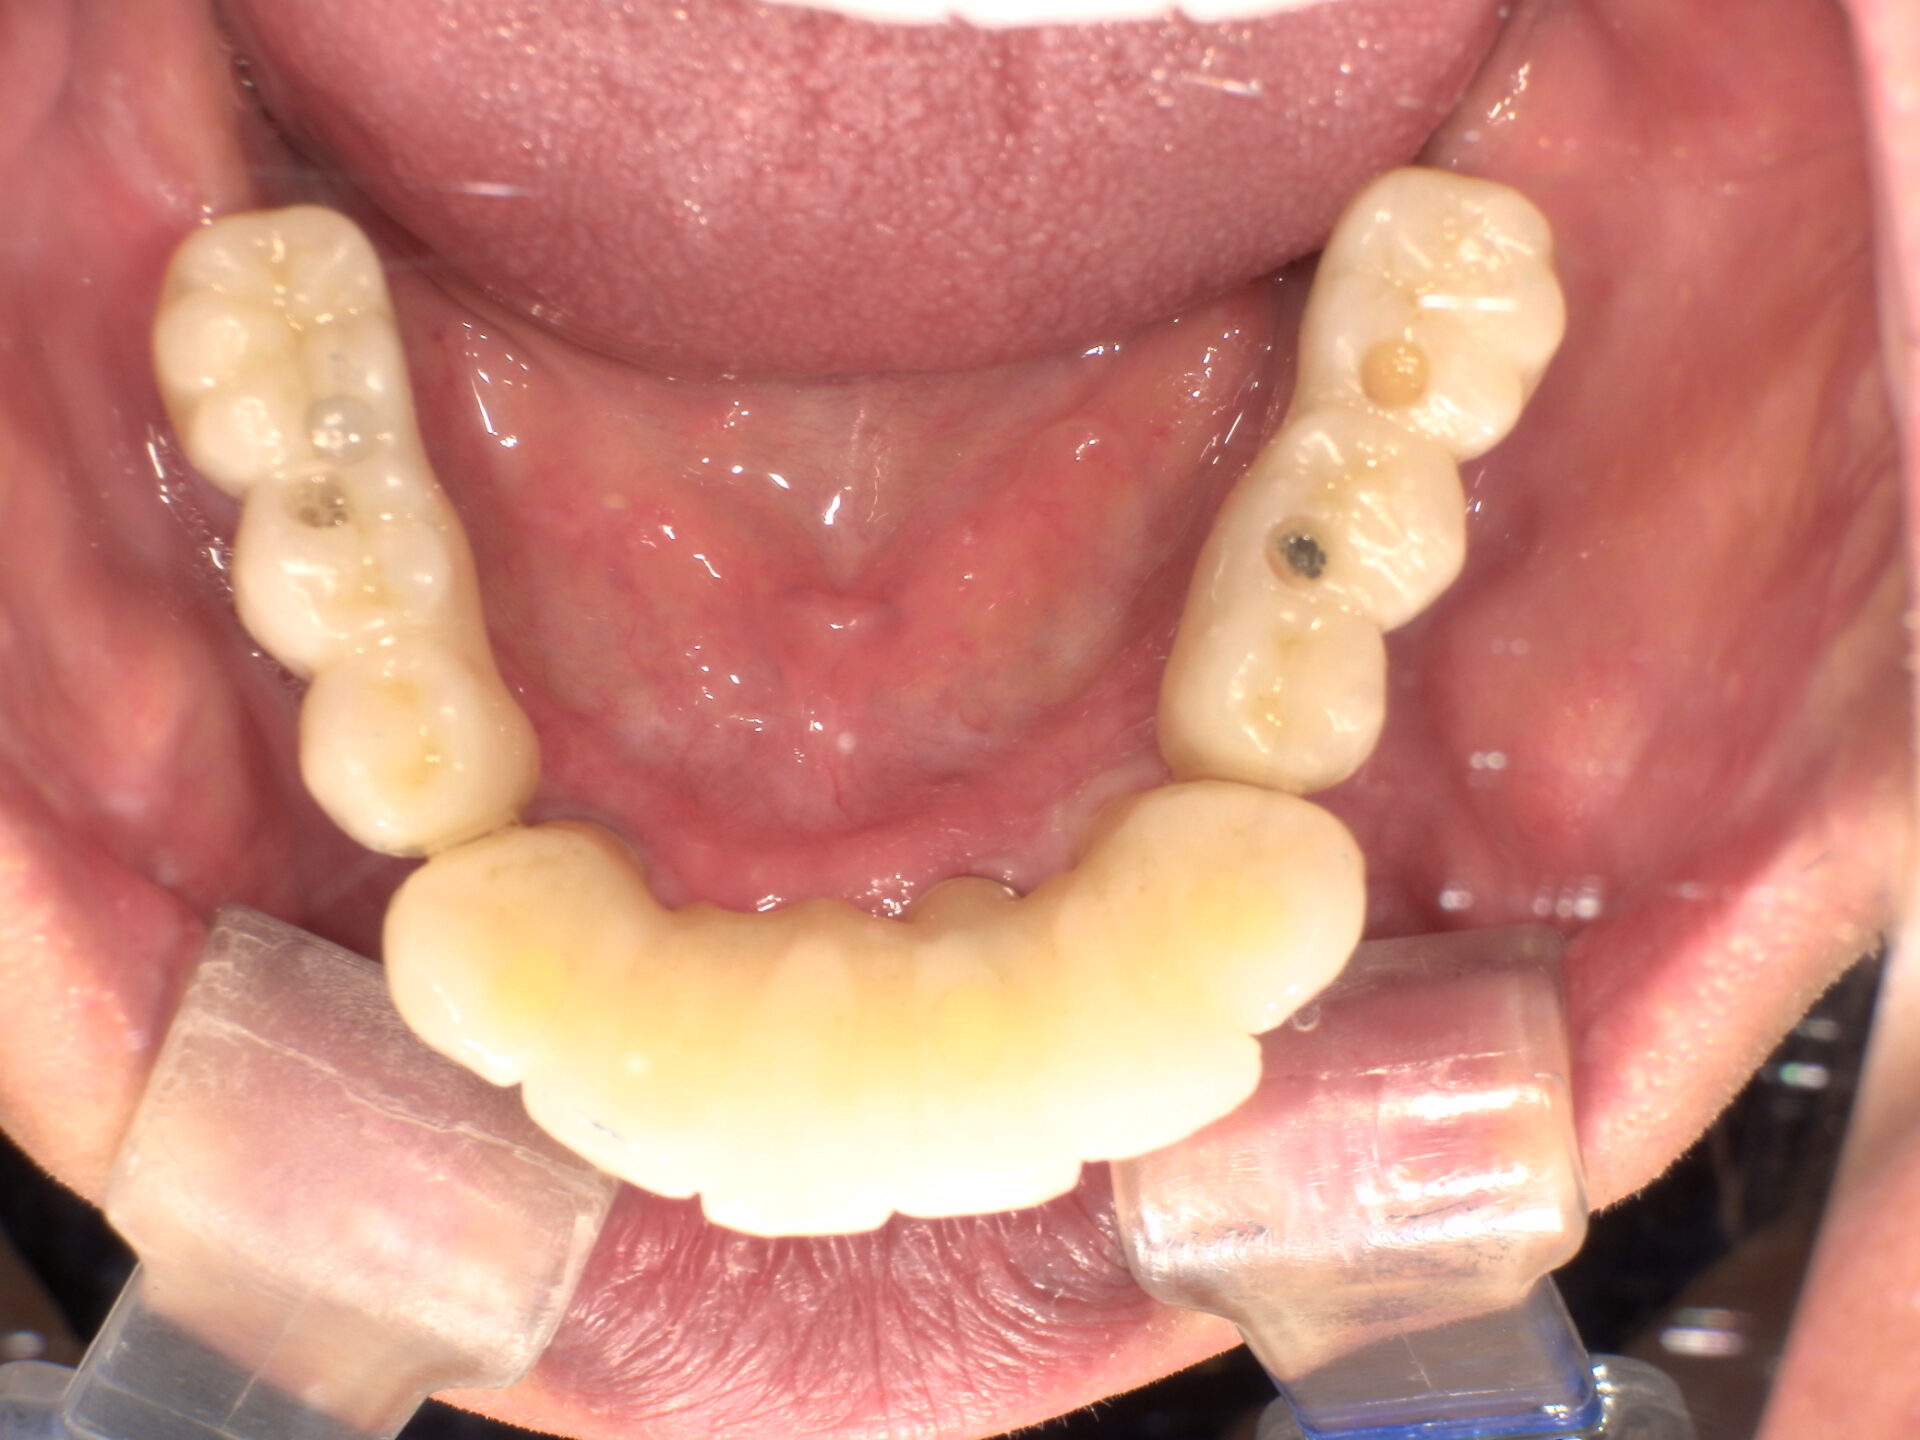

before

after

患者さんの年齢 50代 男性 症状 何も噛めない 治療内容 インプラント治療(オールオン4) 費用 費用900万(税抜) 治療期間・回数 治療期間2年・通院回数12回 メリット なんでも噛めるようになる 見た目が綺麗 デメリット・リスク 骨造成などで費用が増える場合がある - インプラント治療